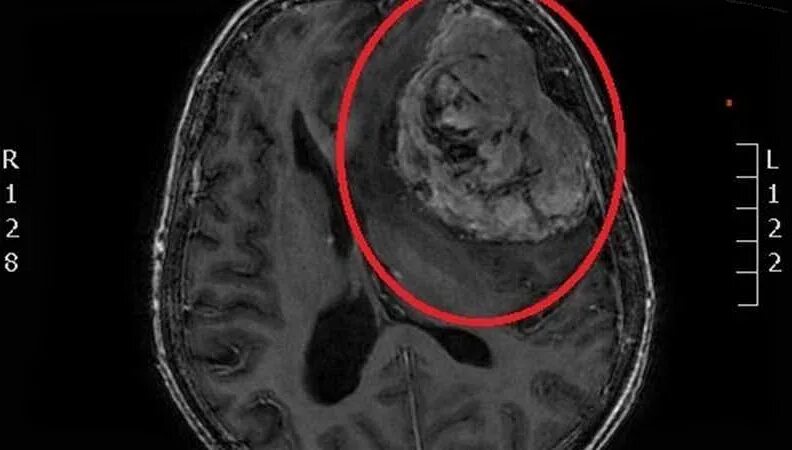

Сколько живут с доброкачественной опухолью головного мозга